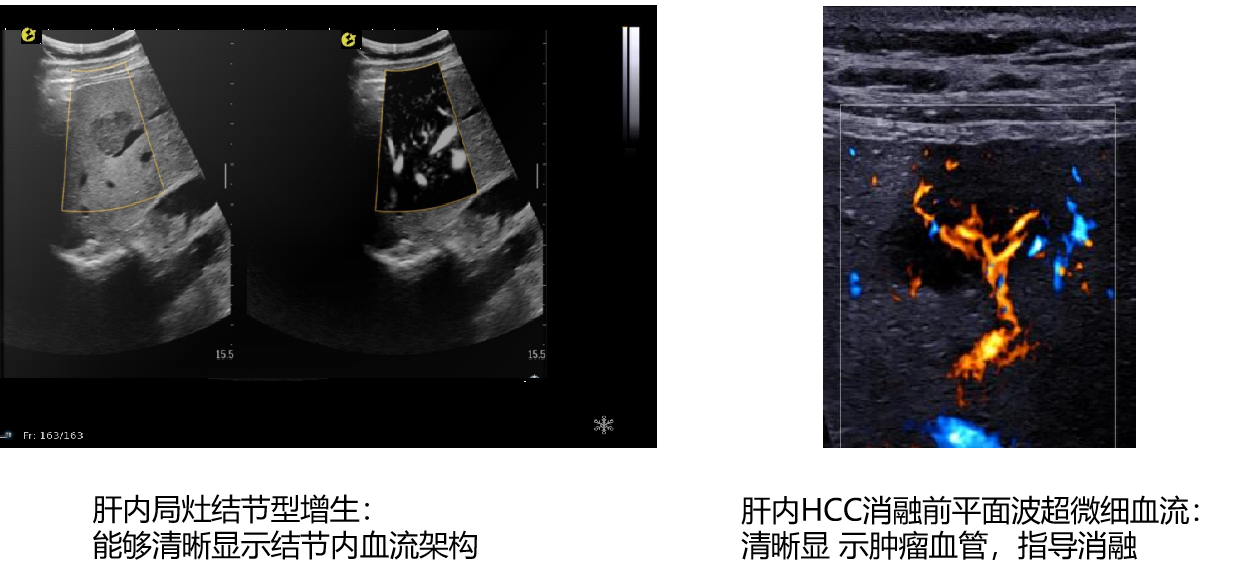

平面波超微细血流显像

能够提供更多真实的组织细小及末梢血管的血流信息,直观的观察组织内部的血管架构及血流形态的情况,提供临床更多有价值的诊断信息。

image.png